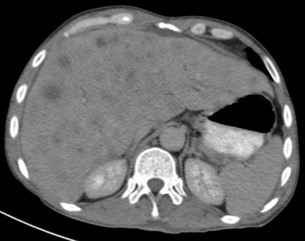

Gastric abnormalities show nonspecific gastrointestinal symptoms and similarly radiological findings. Intra and extra luminal gastric wall thickening are the most common finding in benign and malignant pathologic process. This aim of this case report was to describe several characteristics such as the location and size of the lesion, involvement of the gastric wall and surrounding structures, calcifications, and contrast enhancement pattern which can assist in radiological diagnosis. Several cases at our institution have similar gastrointestinal complaints, however, there were different lesions characteristic found in contrast enhanced abdominal CT scan. The first case 72-years-old man experienced hematemesis with radiologic finding diffuse gastric mucosal thickening as well as homogenous contrast enhancement but without calcification. The second case 37-years-old man complaint dizziness and melena with radiologic finding large tumor more than 10 cm in size, amorph calcification and heterogenous contrast enhancement. The last 60-years-old man case experienced melena and hematemesis, from abdominal CT scan showed irregular gastric mucosal thickening with heterogenous contrast enhancement and fat stranding around the lesion, without calcification. Methods used in these cases were contrast-enhanced abdominal CT scan, esophagogastroduodenoscopy (EGD), and biopsy in order to determine the diagnosis. Contrast-enhanced abdominal CT scan plays a vital role in describing the lesion characteristics which affects the determination of treatment options and future prognosis.